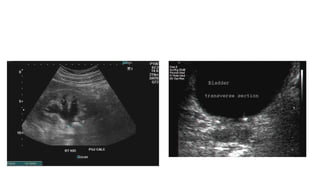

• #10ย Scan shows mild dilatation of the pelvis as well as the calyces of the right kidney suggesting mild hydronephrosis. The left kidney also appears to be affected similarly. This must be differentiated from mild dilatation of the renal pelvis alone, which is physiological and transient; this means that on emptying of the urinary bladder, this appearance should disappear. Multiple lower-pole and renal pelvic echoreflective calculi showing acoustic shadowing are associated mild hydronephrosis.

• #13ย Sonography of the abdomen showed hydronephrosis of the right kidney with a moderately large calculus (14mm.) at the right Pelvi-ureteric junction (arrows). Such calculi cause partial obstruction of the renal pelvis and may cause severe ureteric colic. 2nd image shows multiple, small calculi (3 to 4 mm. in size) in both ureters.

• #19ย An irregular, echogenic, shadowing structure is seen within the bladder. The appearance of the structure resembles a toy jack - hence the designation jackstone.